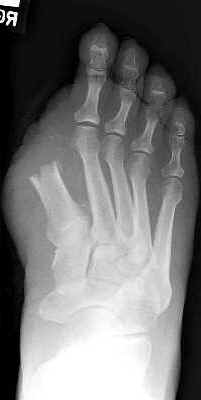

Second toe amputation with resultant hallux valgus

deformity. This is a common complication of second toe amputations and occurs

because the great toe tends to drift toward the third to fill the gap left by the

amputation.